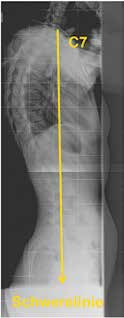

Das neue Konzept „F. B. I.“ (Full Balance Integrated) von J. C. LeHuec bietet nachvollziehbare Lösungsansätze für den Wirbelsäulenchirurgen und liefert damit viele Erkenntnisse, die auch in der Orthesenversorgung so manchen Erfolg oder Misserfolg erklären können 14 (Abb. 5).

Folgende radiologische Parameter werden aktuell verwendet:

- Die Schwerelinie von C7 sollte physiologisch die Deckplatte von S1 schneiden.

- Zum funktionellen Parameter wird der Sacral Slope (SS; Kreuzbeinneigung) = Winkel zwischen einer Deckplattenparallelen S1 mit der Horizontalebene.

- Pelvic Tilt (PT; Beckenkippung) = Winkel zwischen der Lotlinie durch den Femurkopf und der Verbindung zur Sakrumbasis.

- Pelvic Incidence (PI; Tiefe des Beckens) = Winkel zwischen der Verbindungslinie vom Hüftkopfzentrum zur Mitte der Deckplatte S1 und einer Linie, die in einem rechten Winkel zur Deckplatte S1 steht. Dies bildet ein Maß für die Tiefe des Beckens und wird so zum morphologischen Parameter.

- Die Flexion der Hüftgelenke wird durch den Femur Obliquity Angle (FOA; Hüftflexionseinstellung) = Winkel des Femurs zur Vertikalen beschrieben.